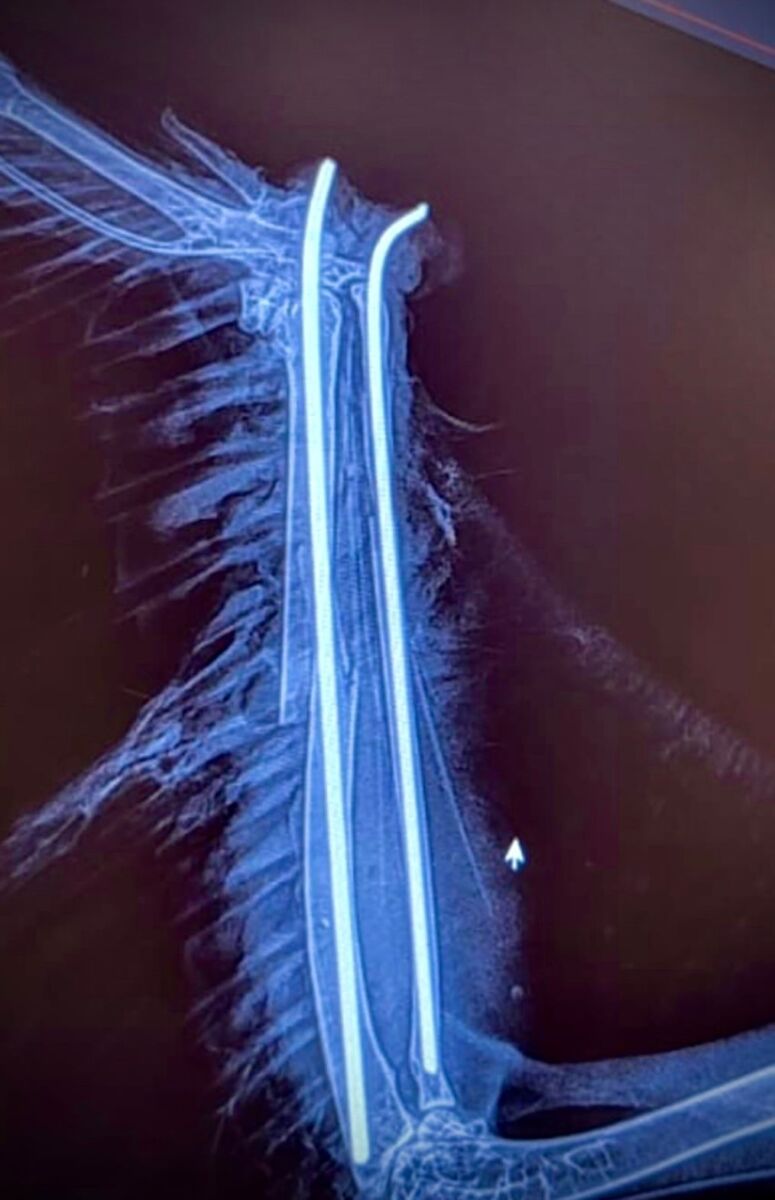

Rocco è stato trovato ferito vicino a Bressanone e presentava una complessa frattura al radio e all’ulna. Il dottor Stefano Capodanno, membro dell’equipe, ha dettagliato il processo di recupero: “Dopo una prima fase di stabilizzazione con antidolorifici e antiinfiammatori, e l’avvio di una terapia antibiotica per le lesioni ai tessuti molli, abbiamo proceduto all’intervento chirurgico con l’inserimento di un chiodo centro midollare per allineare i monconi ossei.”